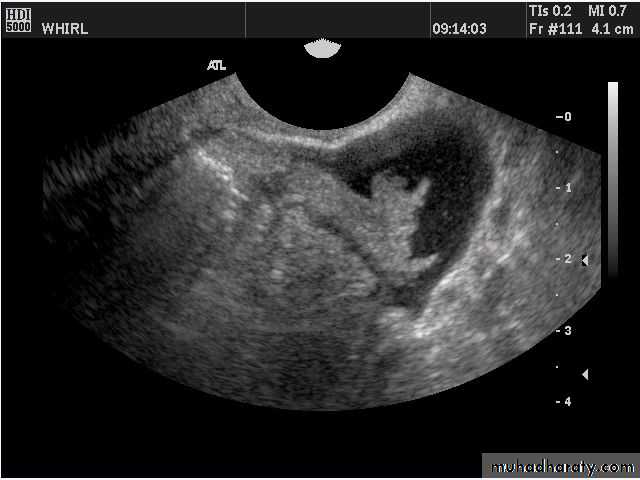

Transabdominal scanned image

• Rupture of hemorrhagic ovarian cyst:

Transvaginal scanned image